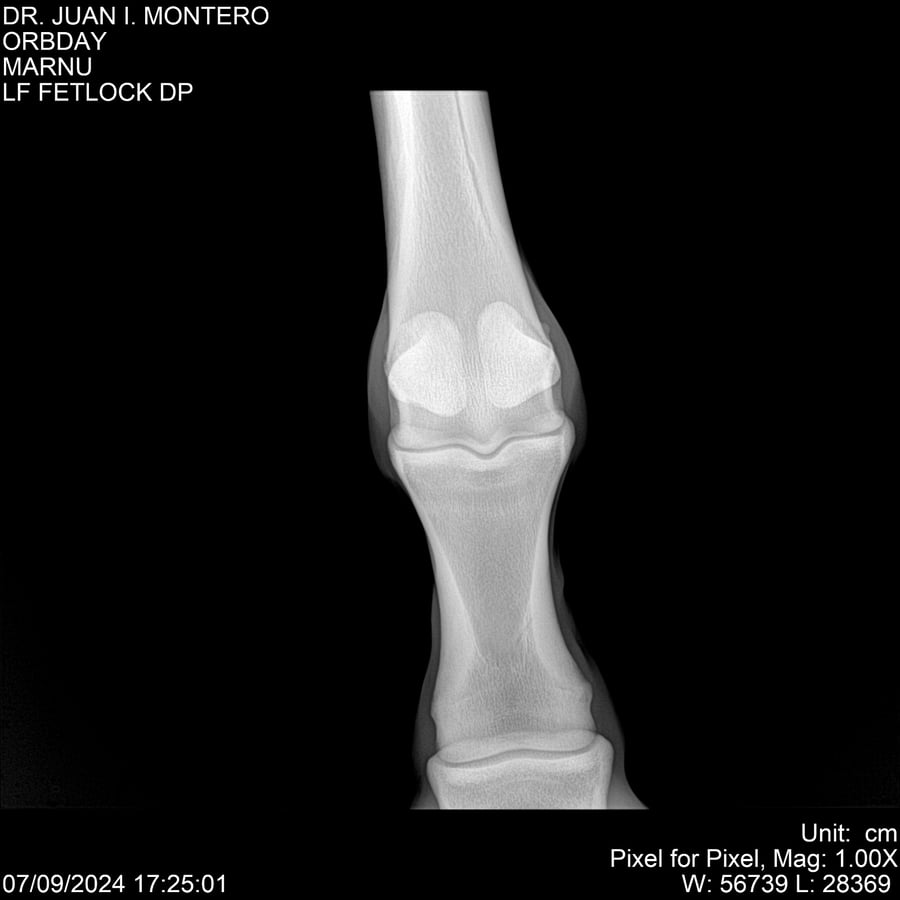

• Empresa: Abelenda N. R., Walter Hugo